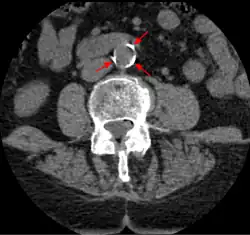

CT image of atherosclerosis of the abdominal aorta. A woman of 70 years old with hypertension and dyslipidemia.

Doppler ultrasound of right internal carotid artery with calcified and non-calcified plaques showing less than 70% stenosis